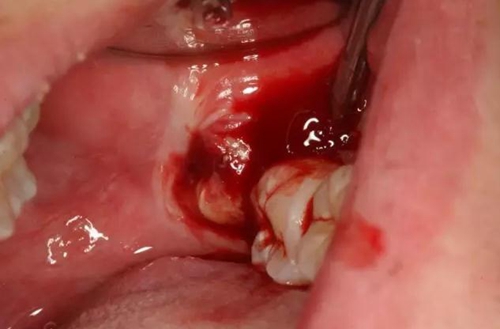

圖6.患者年輕、骨質(zhì)比較軟。牙挺放置在38牙根近中,先用推力豎直38牙冠、然后用挺力直接挺出38

圖7.炎癥期拔牙出血較多、放置止血海綿一塊,壓迫止血半小時(shí)